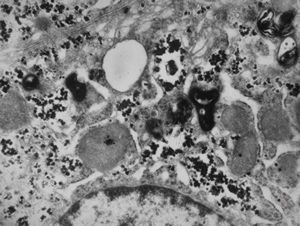

M,66y. | siderosomes

M,66y. | hemosiderin - siderosomes